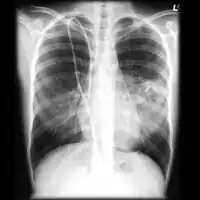

Chest X-ray: Angioinvasive aspergillosis